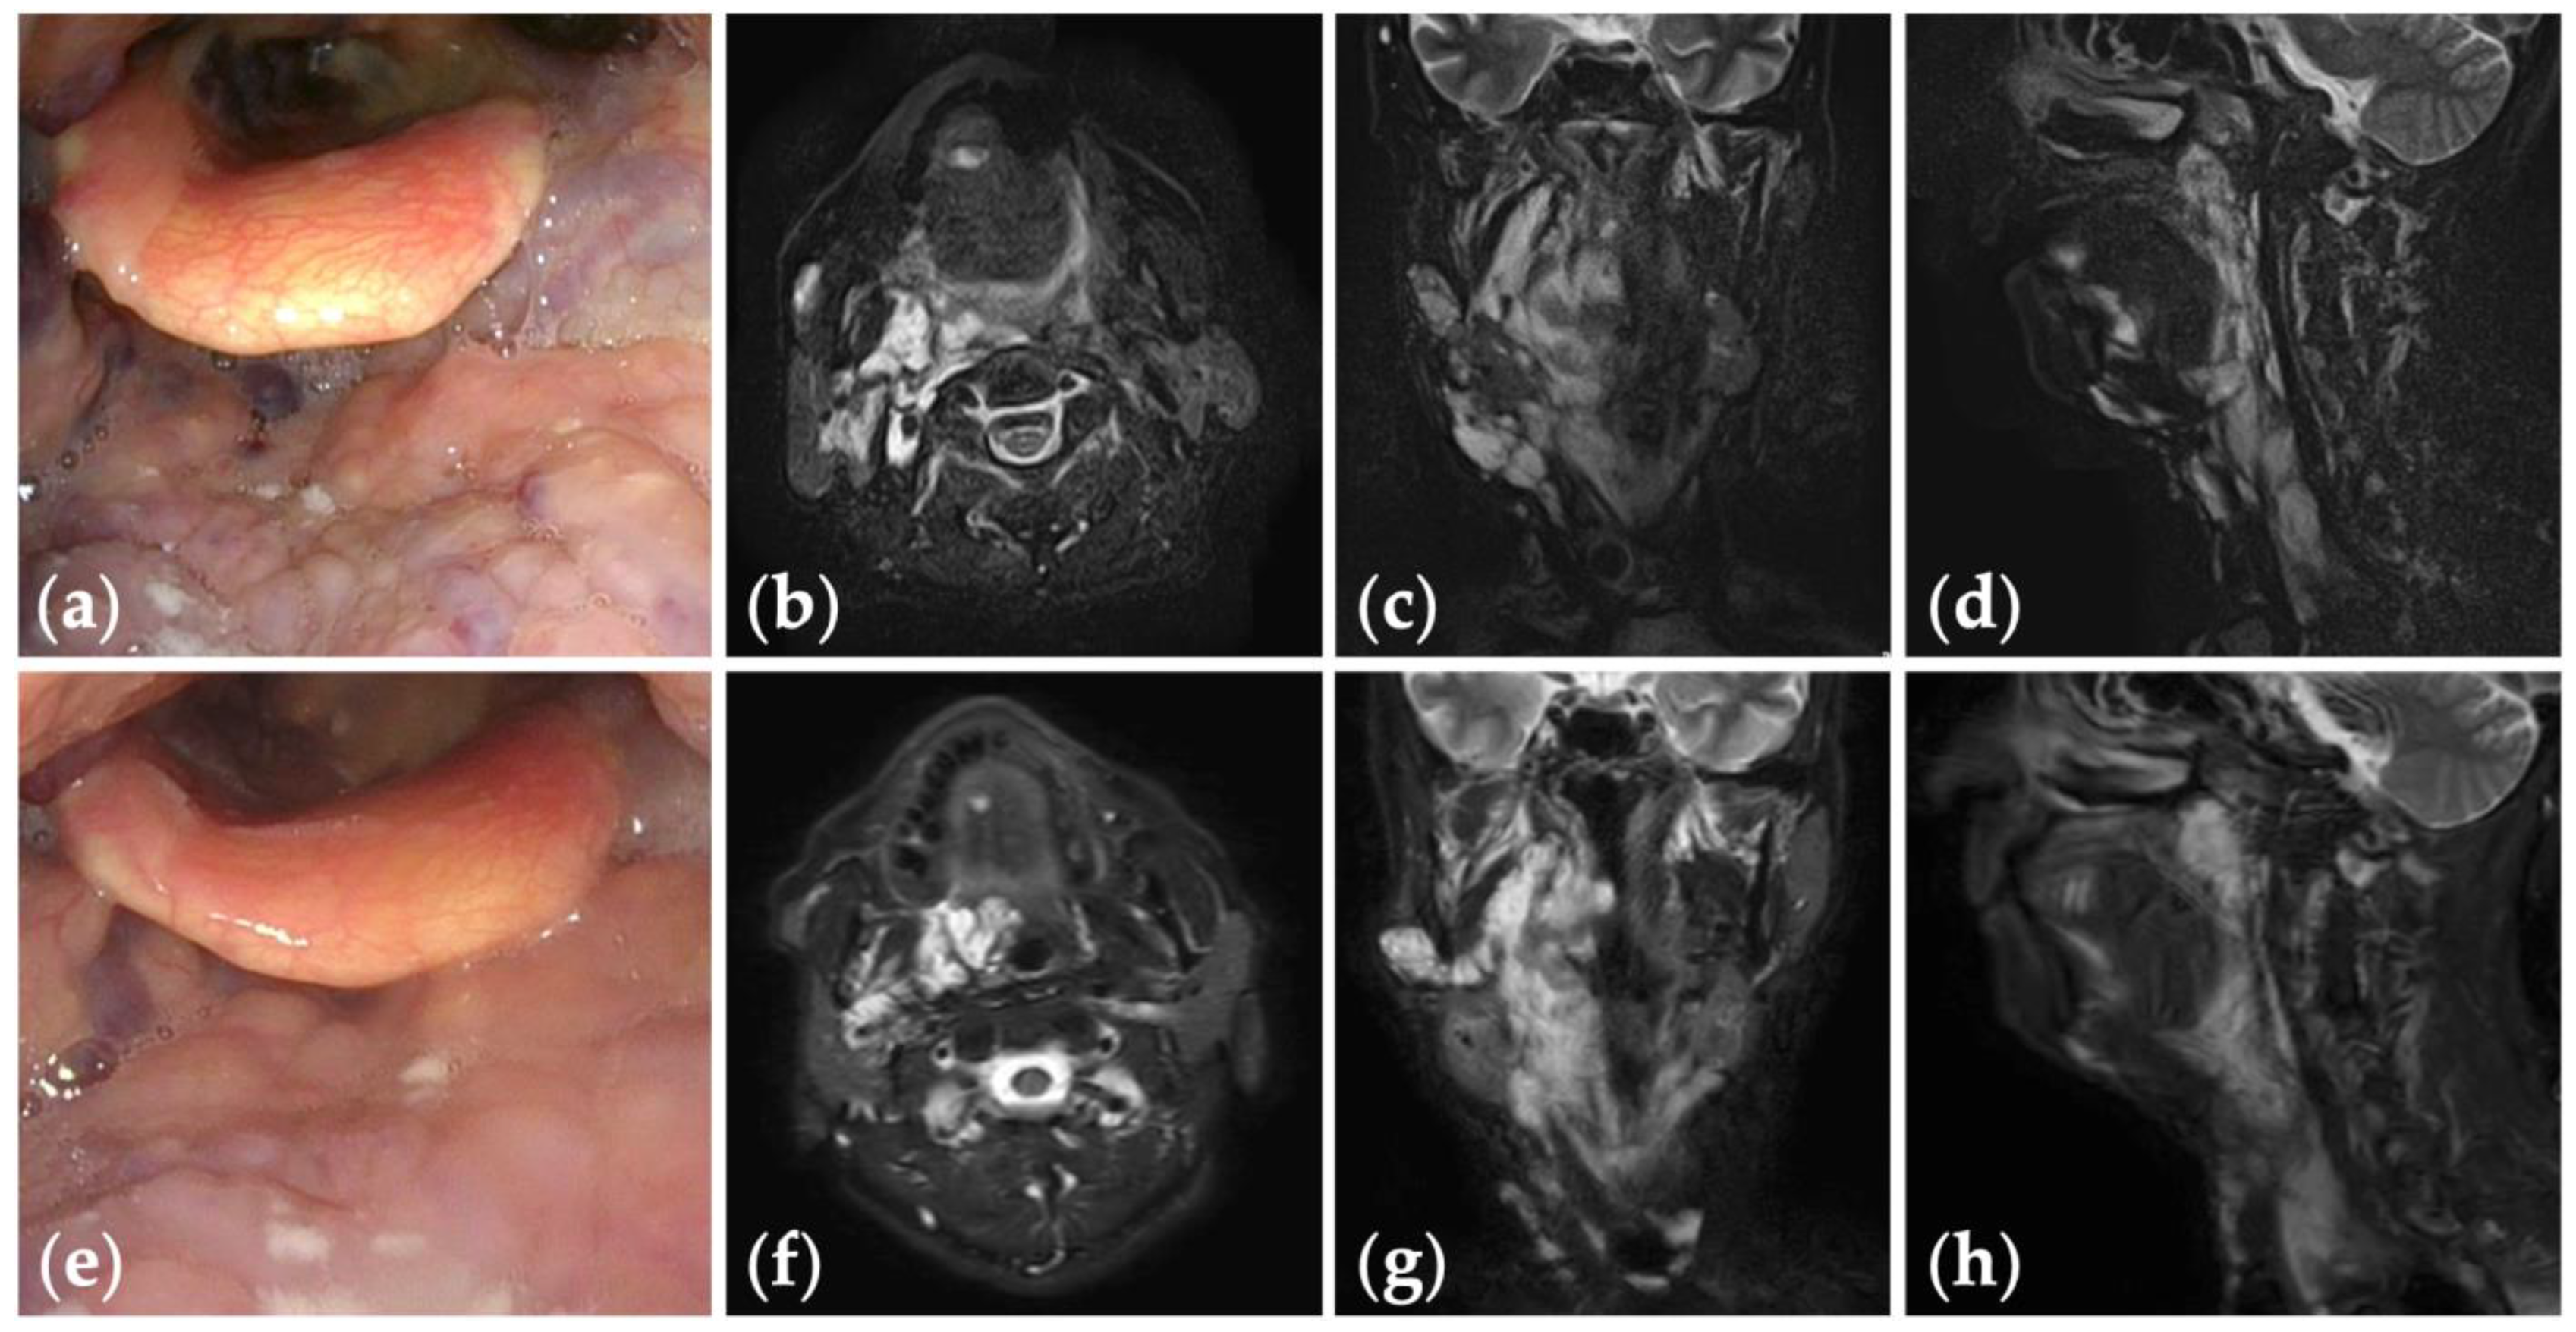

Patient 2 graded “good” for treatment outcomes after seven sessions of fluoroscopy- and endoscopy-guided transoral sclerotherapy: (a) an initial endoscopic photograph of the pharynx of a 71-year-old man with oropharyngolaryngeal venous malformation, and (e) the latest endoscopic photograph six months after the fifth sclerotherapy session at the age of 73 years; (b–d) short tau inversion recovery T2-weighted magnetic resonance images before treatment, and (f–h) three years after the final sclerotherapy session at the age of 78 years.